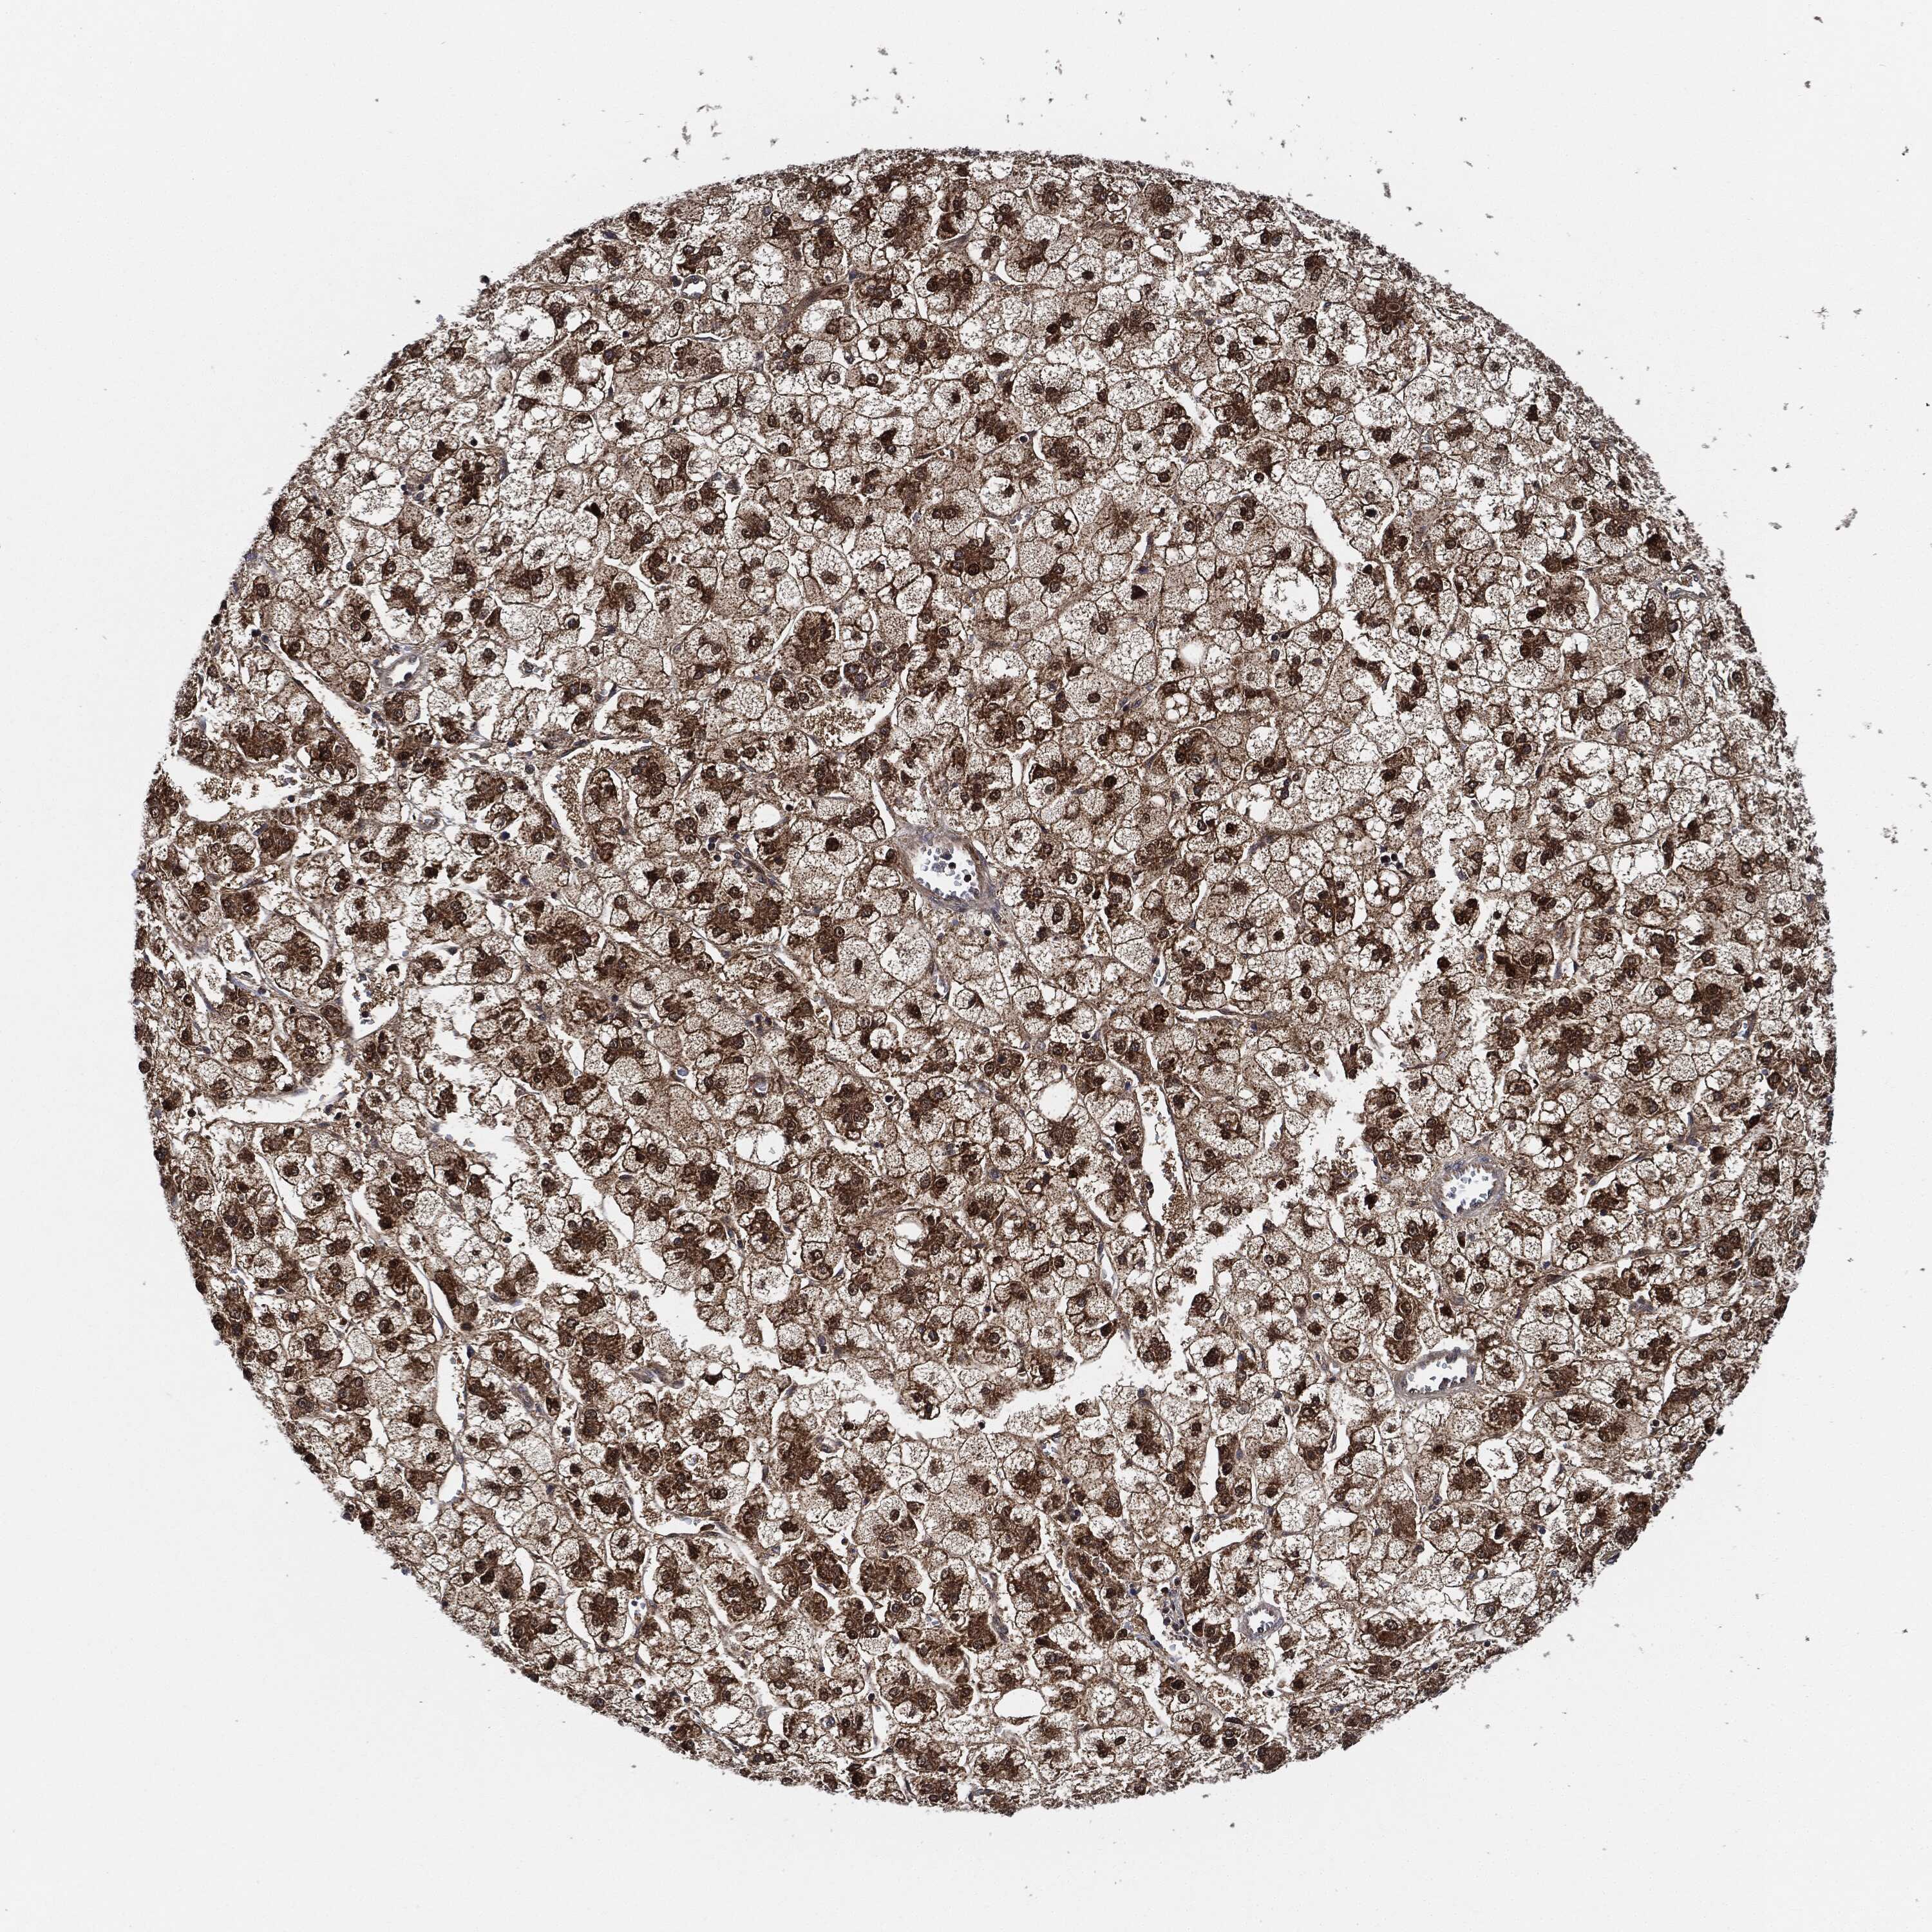

LIVER CANCER - Protein expressioni

A mouse-over function shows sample information and annotation data. Click on an image to view it in a full screen mode. Samples can be filtered based on level of antibody staining by selecting one or several of the following categories: high, medium, low and not detected. The assay and annotation is described here.

Note that samples used for immunohistochemistry by the Human Protein Atlas do not correspond to samples in the TCGA dataset.

Antibody stainingi

Antibody staining in the annotated cell types in the current human tissue is reported as not detected, low, medium, or high, based on conventional immunohistochemistry profiling in selected tissues. This score is based on the combination of the staining intensity and fraction of stained cells.

Each image is clickable and will lead to virtual microscopy that enables deeper exploration of all samples and also displays staining intensity scores, fraction scores and subcellular localization as well as patient and tissue information for each sample.

Antibody HPA002633

Antibody HPA046758

Antibody CAB010906

Staining

High

Medium

Low

Not detected

Intensity

Strong

Moderate

Weak

Negative

Quantity

>75%

75%-25%

<25%

None

Location

Nuclear

Cytoplasmic/membranous

Cytoplasmic/membranous,nuclear

Cholangiocarcinoma

Carcinoma, Hepatocellular, NOS